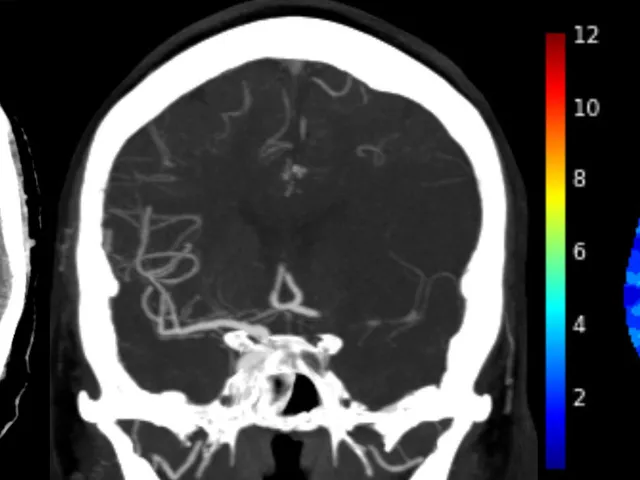

The fellowship focuses on CT-based stroke imaging, including NCCT, CTA, and CTP, emphasizing their combined use for ischemic and hemorrhagic strokes. It includes case studies addressing clinical challenges, rare stroke causes, differential diagnoses, and pitfalls. Vascular anatomy and physiology are covered to enhance understanding of imaging implications.

The fellowship will cover the entire field of CT-based stroke imaging, including NCCT, CTA and CTP. Emphasis will be on the combined utilization of NCCT, CTA and CTP in a comprehensive stroke imaging package for ischemic stroke and NCCT and CTA for hemorrhagic stroke.

The area will be illustrated by a number of illustrative cases, highlighting the combined utilization of NCCT, CTA and CTP and addressing some clinical challenges in stroke imaging including rare causes of stroke as well as some of the most important differential diagnosis and pitfalls. Vascular anatomy and physiology will be included when necessary to understand the implications on imaging and vice versa.